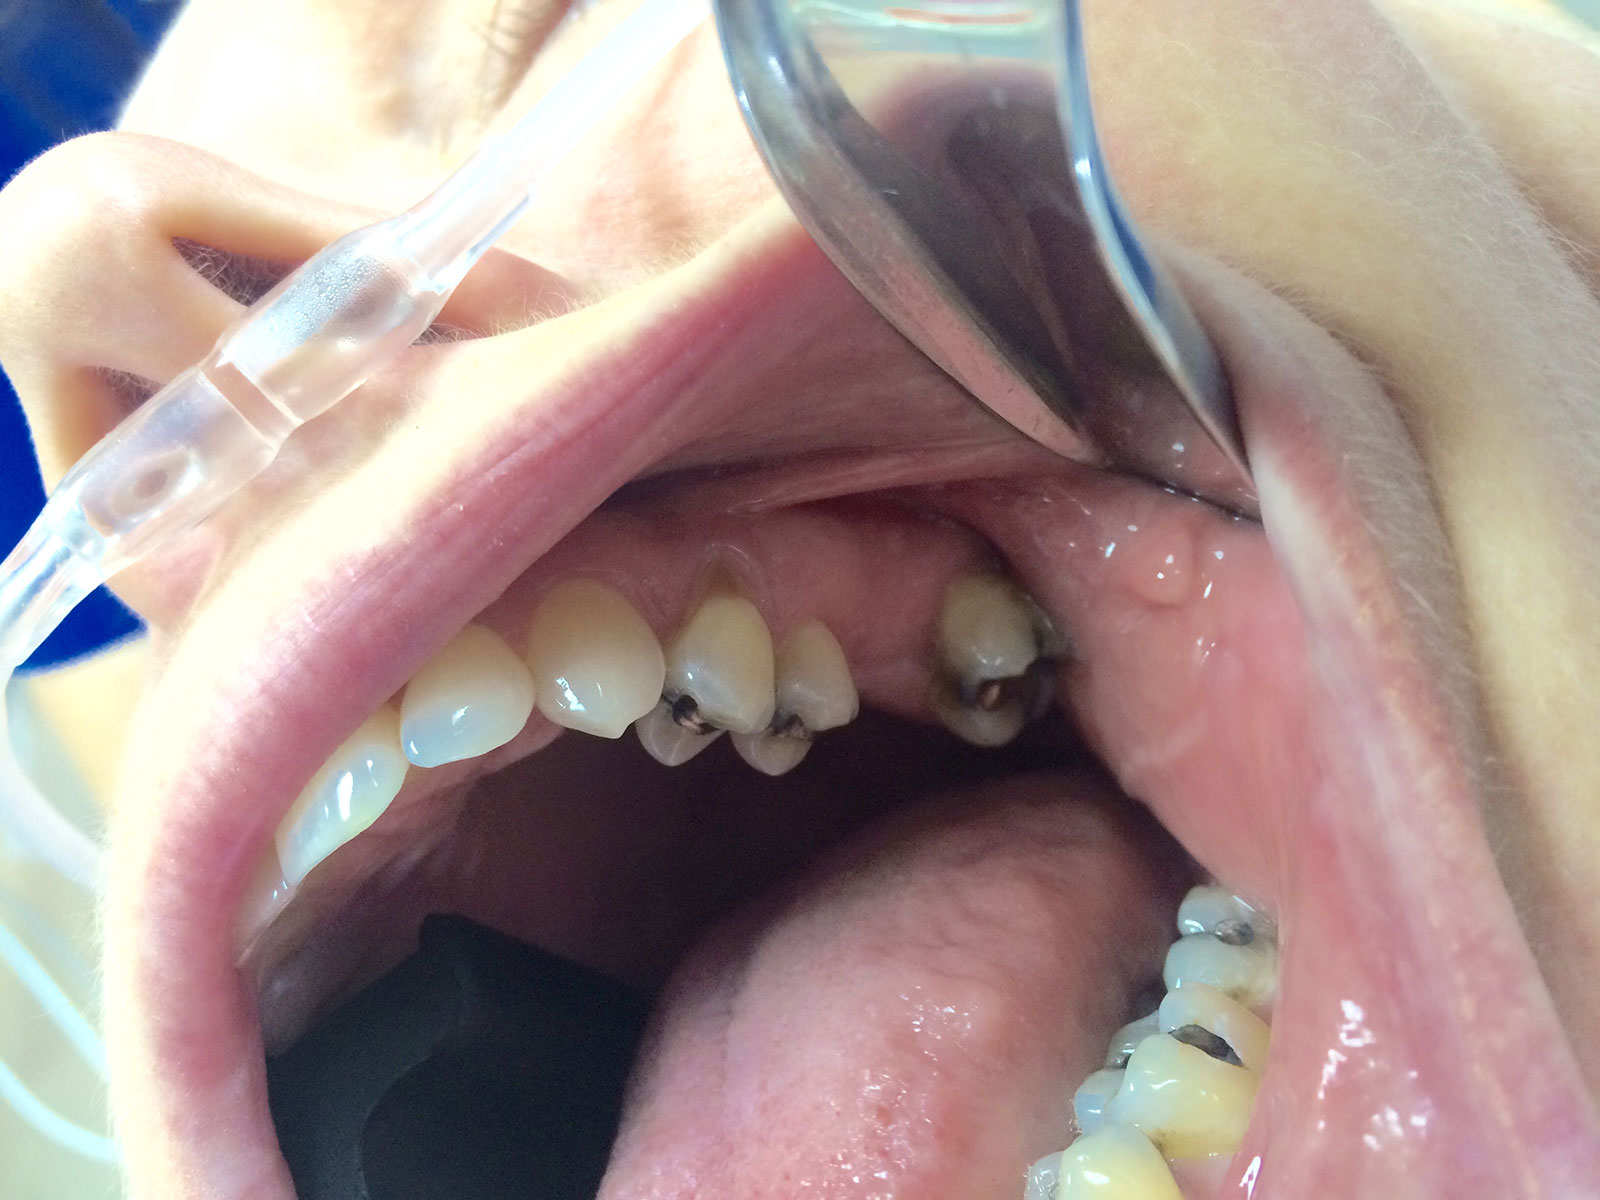

Sinus Grafting Procedures

A sinus grafting procedure, also known as a sinus augmentation, is for patients who have insufficient natural bone in the areas where dental implants are needed. They are long lasting, strong and sturdy, and fit and function like natural teeth. The procedure involves adding bone, either your own natural bone from another part of the body, from a donor or made of processed or synthetic bone material, and placing it below the sinus so that the implants can be placed. After the bone has healed and developed, usually around four to 12 months, the dental implants can be placed.

The photos on this website are from real surgeries performed by Dr. Ulloa. Due to the

graphic nature of the images and content, viewer discretion is advised.

Click to enlarge images